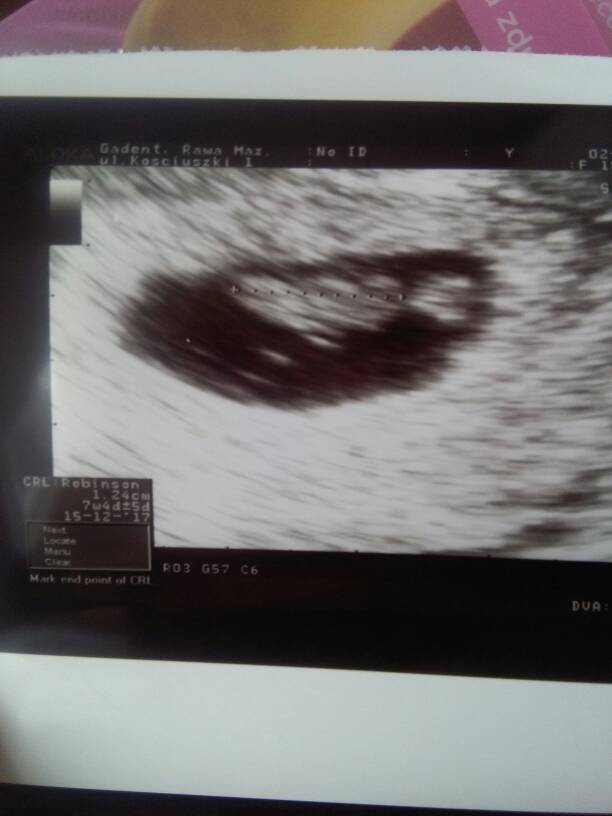

My po wizycie

Na pierwszym zdjęciu widać rączkę, na drugim rączki, nóżki, na trzecim jest do góry nogami. Ruszał się, wręcz tańczył, serduszko tłucze jak szalone. Wszystko jest pięknie! Lekarz zachwycony, a my przeszczęśliwi![]()